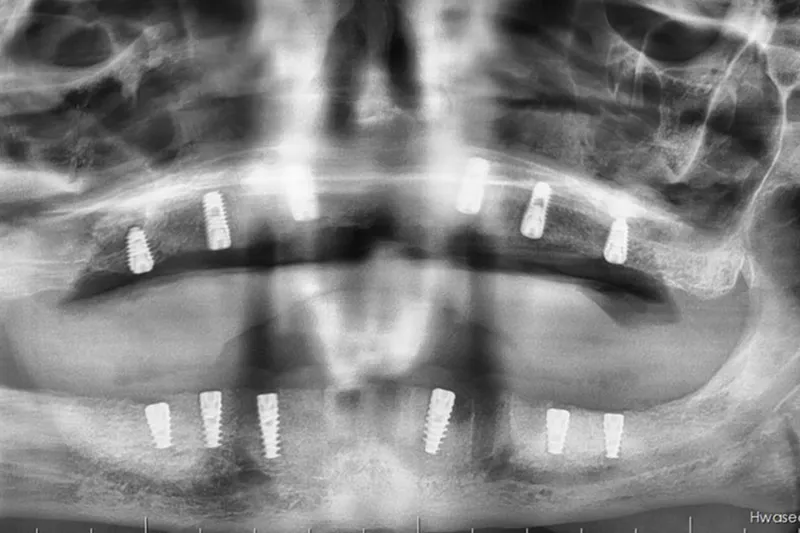

Batman Ağız ve Diş Sağlığı Hastanesi’nde ileri cerrahi gerektiren bir vakada, genel anestezi altında açık sinüs lift (eksternal sinüs lift) ameliyatı ile birlikte implant uygulaması yapıldı.

Hastanede tedavi gören 55 yaşındaki Hüsnü Üner’de sağ ve sol üst çene arka bölgelerinde ileri düzey sinüs sarkması ve kemik yetersizliği tespit edildi. Lokal anestezi ile tedavi edilmesi mümkün olmayan vakada, Ağız, Diş ve Çene Cerrahisi Uzmanı Uzm. Dt. Ebru Baydan Çol tarafından genel anestezi altında her iki üst çeneye aynı seansta açık sinüs lift ameliyatı uygulandı.

Cerrahi işlemin ardından hastanın üst ve alt çenesine implantlar yerleştirildi. Ameliyat sonrası genel durumu stabil olan hastanın iyileşme sürecinin planlandığı şekilde devam ettiği bildirildi.